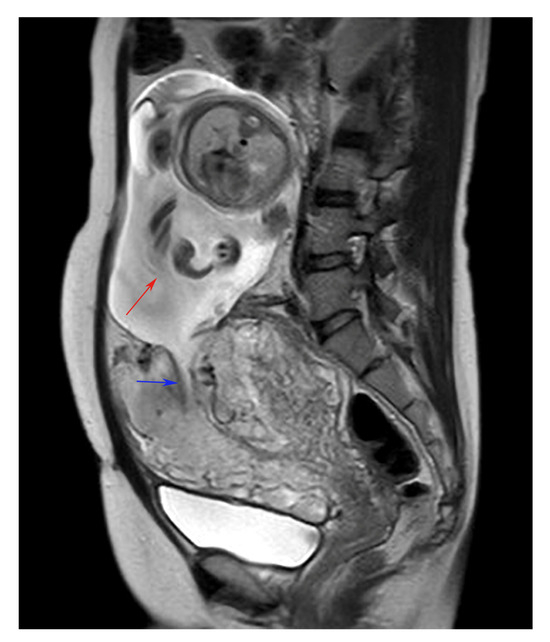

Fetus in the Abdominal Cavity After Uterine Rupture in a Primigravida Post-Adenomyosis Enucleation

Kamata, S.; Ando, H.; Matsuda, E.; Aoki, A.; Komatsu, A.; Kawana, K. Fetus in the Abdominal Cavity After Uterine Rupture in a Primigravida Post-Adenomyosis Enucleation. Diagnostics 2024, 14, 2470. https://doi.org/10.3390/diagnostics14222470